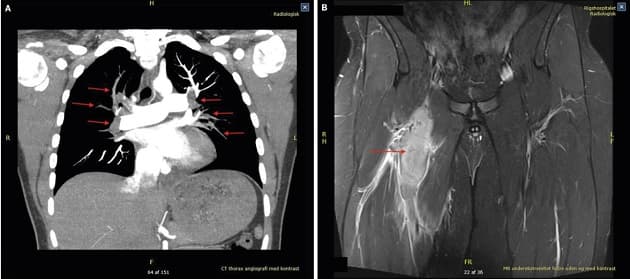

Hansen og Lundstrøm beskriver en sygehistorie, hvor en 15-årig dreng uden familiære dispositioner til tromboemboliske sygdomme blev akut indlagt med åndenød, hoste, smerter i brystet og i højre lyske. Torakal CT-angiografi viste multiple lungeembolier (LE) og MR-skanning af begge ben viste et højresidigt aneurisme i v. femoralis communis med massiv trombedannelse. Forfatterne anfører, at venøse aneurismer i underekstremiteterne ofte fører til recidiverende LE, hvorfor kirurgisk behandling anbefales.